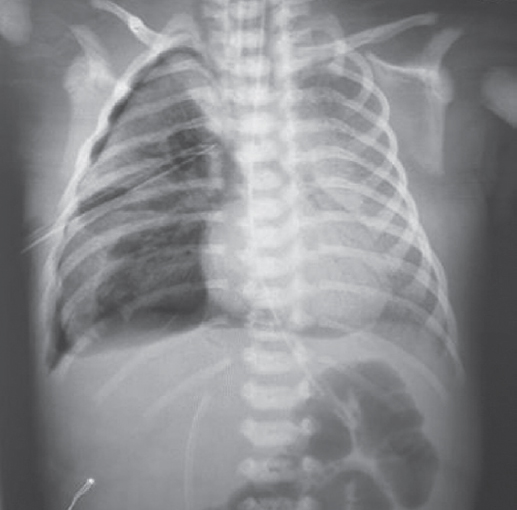

В статье представлен случай успешного лечения острого респираторного дистресс-синдрома у доношенного новорожденного, осложнившегося баротравмой легких, с применением монобронхиального введения экзогенного сурфактанта под рентгенологическим контролем. С целью оценки течения заболевания и эффективности лечения проведен ретроспективный анализ медицинской документации. С первых минут жизни у ребенка отмечались дыхательные расстройства, что стало основанием для проведения неинвазивной искусственной вентиляции легких. В динамике выявлено прогрессирование гиперкапнии и гипоксемии, в связи с чем была выполнена интубация трахеи и начата конвекциональная искусственная вентиляция легких с FiO2 = 1,0. Ключевой элемент терапии, позволивший достичь стабилизации состояния и регрессирования нарушений газообмена с полным выздоровлением пациента, — монобронхиальное введение экзогенного сурфактанта.